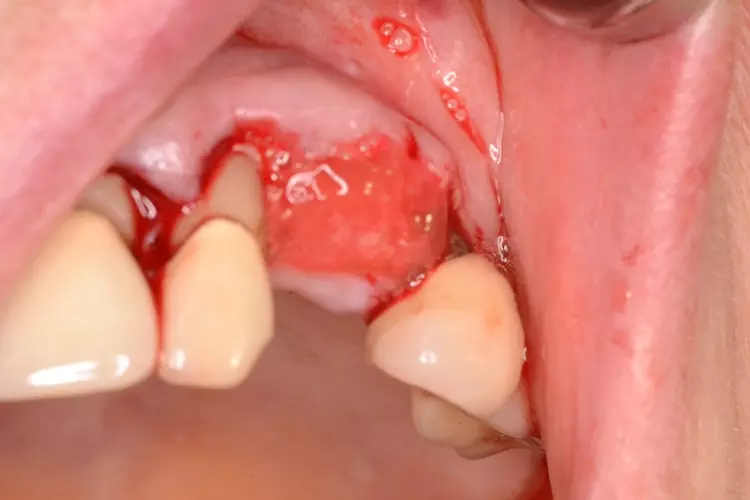

Die Fraktur des stark elongierten Zahnes 21 war für den Patienten der Ausgangspunkt, sowohl die Front des Ober- als auch des Unterkiefers prothetisch überarbeiten zu lassen. Dabei wurde der frakturierte Zahn 21 durch ein navigiert eingesetztes Sofortimplantat ersetzt, während die verschachtelt stehenden Zähne 12 und 42 durch eine Brückenversorgung korrigiert wurden (Abb. 4a-j).